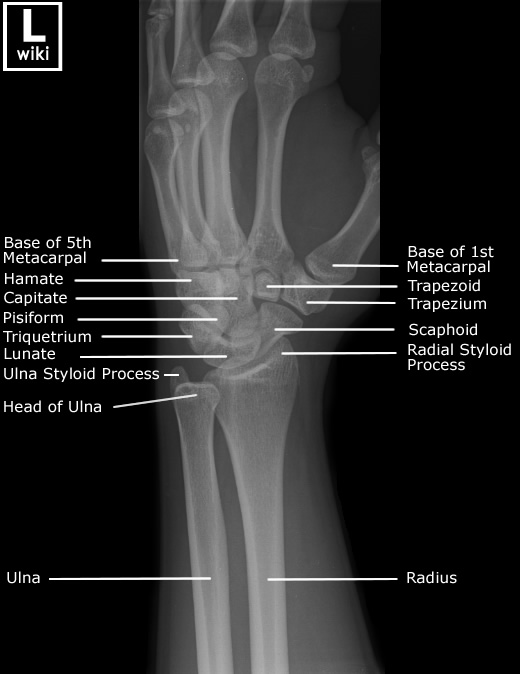

| [Anatomy] Wrist(손목) (0) | 2024.01.15 |